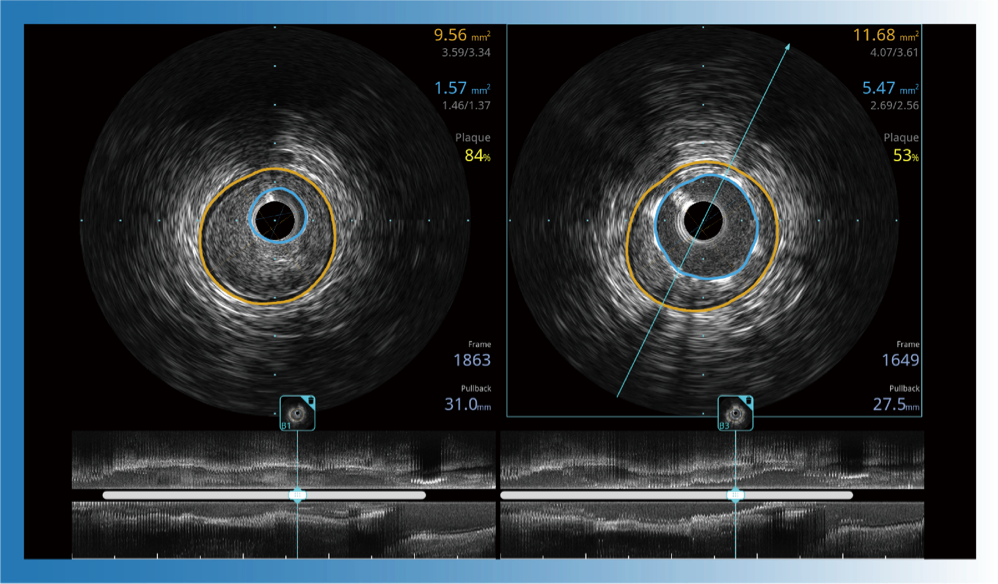

对比传统IVUS导管成像,云顶集团官网宽频IVUS图像的近场支架梁显影更细腻,远场中膜外血管仍清晰可辨,兼顾远中近,兼顾分辨力与穿透深度

治疗前后两次测量录像对比

简化疗效评估

一键智能描迹,自动测量斑块负荷、面积狭窄率等指标,准确率高于90%